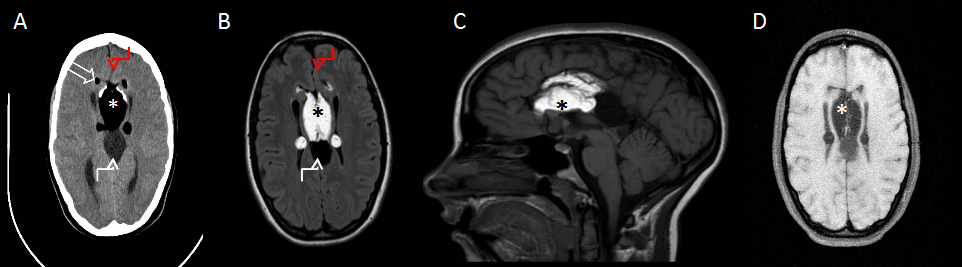

TC axial sin contraste (imagen A): lesión de 4 cm de diámetro máximo y densidad grasa en la cisura interhemisférica (asterisco), con calcificaciones groseras periféricas (flecha hueca). Se evidencia además agenesia del cuerpo calloso (flecha roja) y otra lesión, inmediatamente posterior, bien definida y de densidad similar al LCR (flecha blanca).

RM T1-WI axial y sagital (imagen B y C): lesión hiperintensa en la cisura interhemisférica (asterisco) con septos finos, agenesia del cuerpo calloso (flecha roja) y lesión nodular hipointensa (flecha blanca), localizada más posteriormente.

RM T1-WI fat-sat axial (imagen D): Supresión de la señal de la lesión de mayor tamaño (asterisco), compatible con contenido de grasa.

Agenesia completa del cuerpo calloso con lipoma pericalloso túbulo-nodular voluminoso y quiste de la cisura interhemisférica asociado.